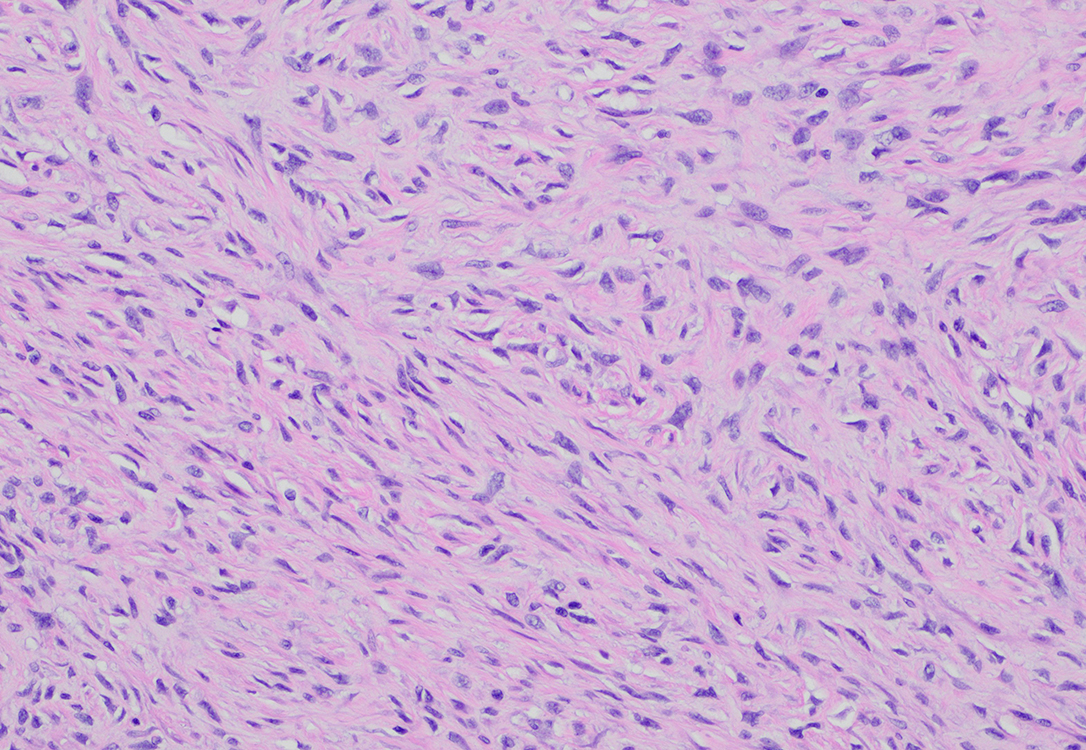

FIgure 2 Low power